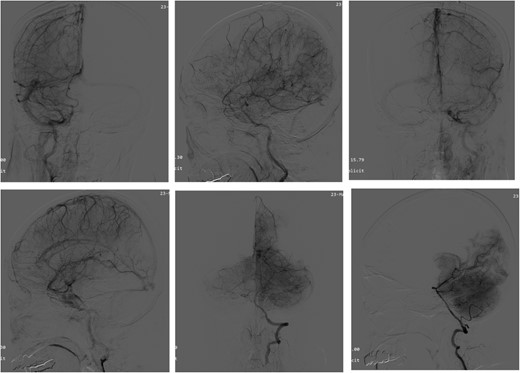

Intraoperative pathologic images (Fig. 1) showed the vascular morphology in the lesion is irregular, with an indistinct hierarchical vascular wall structure and multiple lumen sizes. Brain angiography (Fig. 2) showed no significant vascular malformations.

Angiography of the brain. Brain angiography showing obvious vascular malformations.